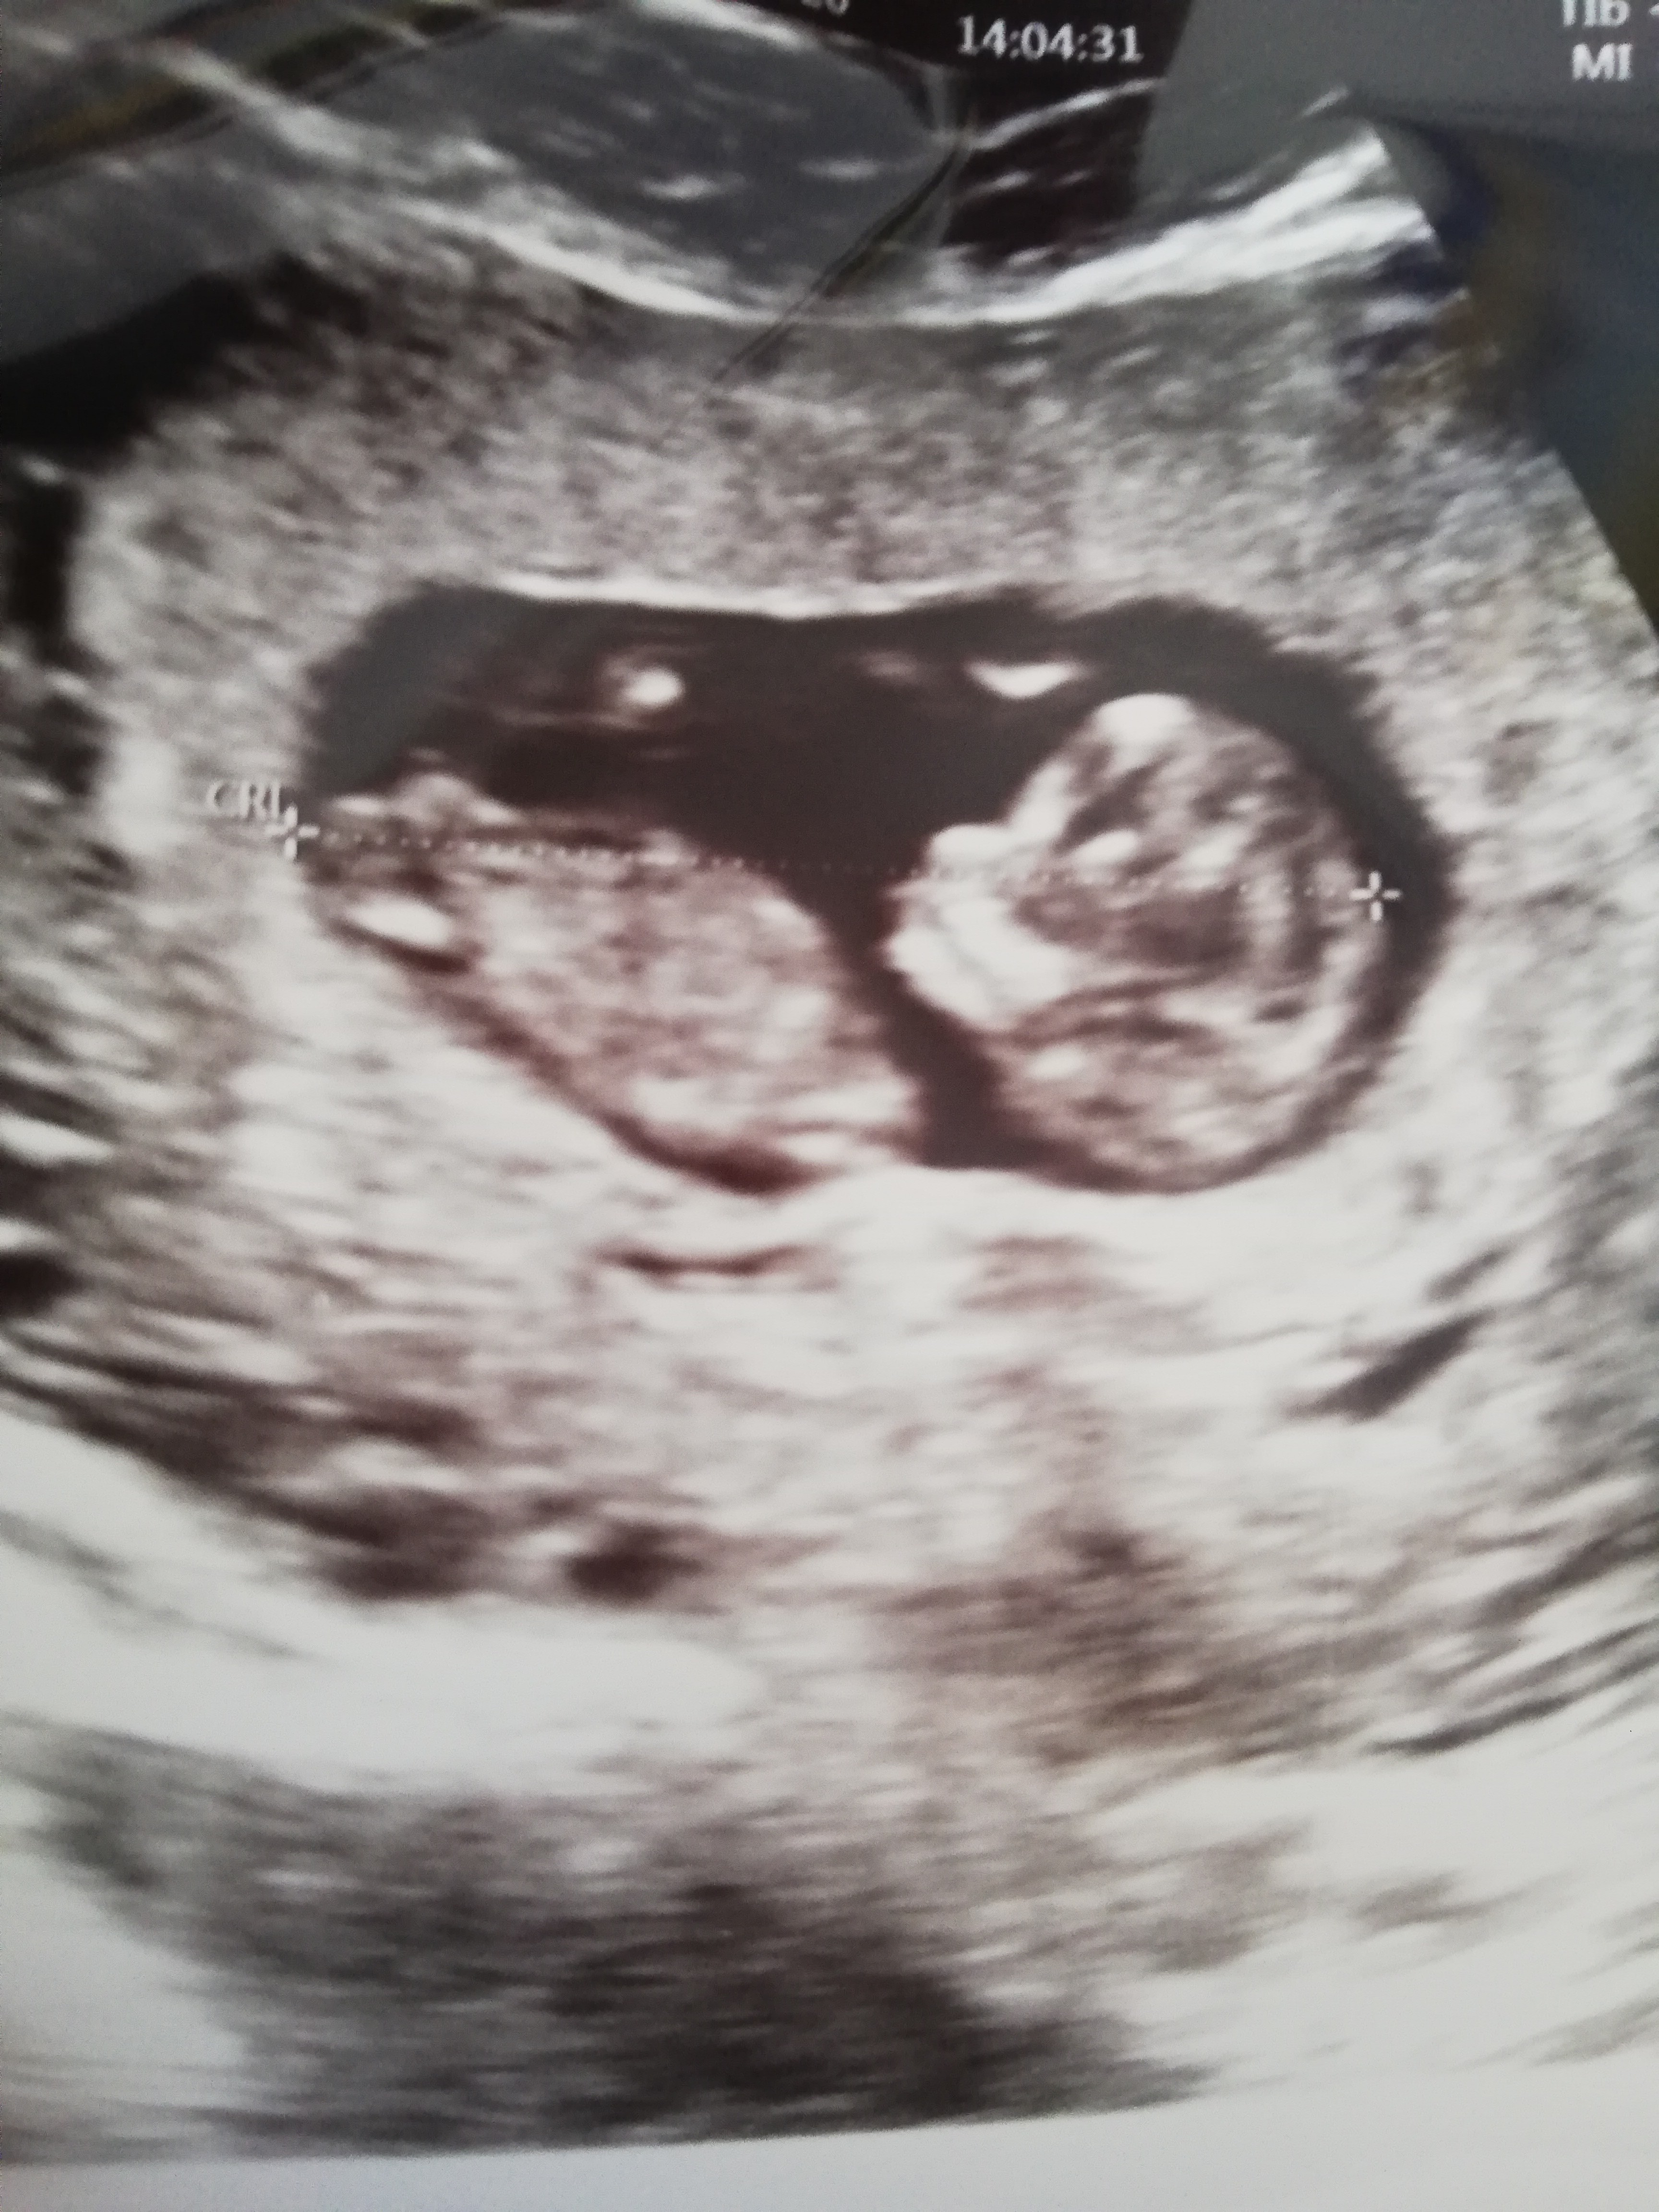

Witajcie Kobietki! 😘 Witam się z Warszawy, mam 33 lata i to moja pierwsza ciąża, dziś 13+3, termin mam wg Om 4.04 a wg usg 3.04 🙂 zdecydowałam się "objawić" bo wreszcie mam siłę coś napisac, do tej pory byłam biernym acz regularnym obserwatorem Waszych rozmów 😉 ja swoją ciąże przechodzę fatalnie, od 7 tygodnia leżę w łóżku bo nie jestem w stanie inaczej funkcjonować, wymioty (a raczej torsje, bo nic prawie nie jem) codziennie do 4 razy, mdłości non stop. Najgorsze jest wychodzenie na badania, wracam jak po drodze krzyżowej, a mąż musi mnie podtrzymywać... To tak w skrócie, pożaliłam się 😁 miłego dnia! 🌼

Hej ☺ Gratulacje🥳 Piękny bobo🥰

Dziękuje :D Jak zapytałam o płeć to Pani stwierdziła, że dziecko leży nie tak i nic nie widać. Moja bliska koleżanka, która rodziła w lutym stwierdziła, że po moim wyglądzie wszystko wskazuje na chłopca z kolei jak zobaczyła, że FHR dziecka to 163 to trochę wskazuje na dziewczynkę bo u niej na grupie wszystkie dziewczynki miały powyżej 155 :D . Sama bardzo chciałabym dziewczynkę, ale zaakceptuje każdą płeć oby tylko dziecko było zdrowe :)